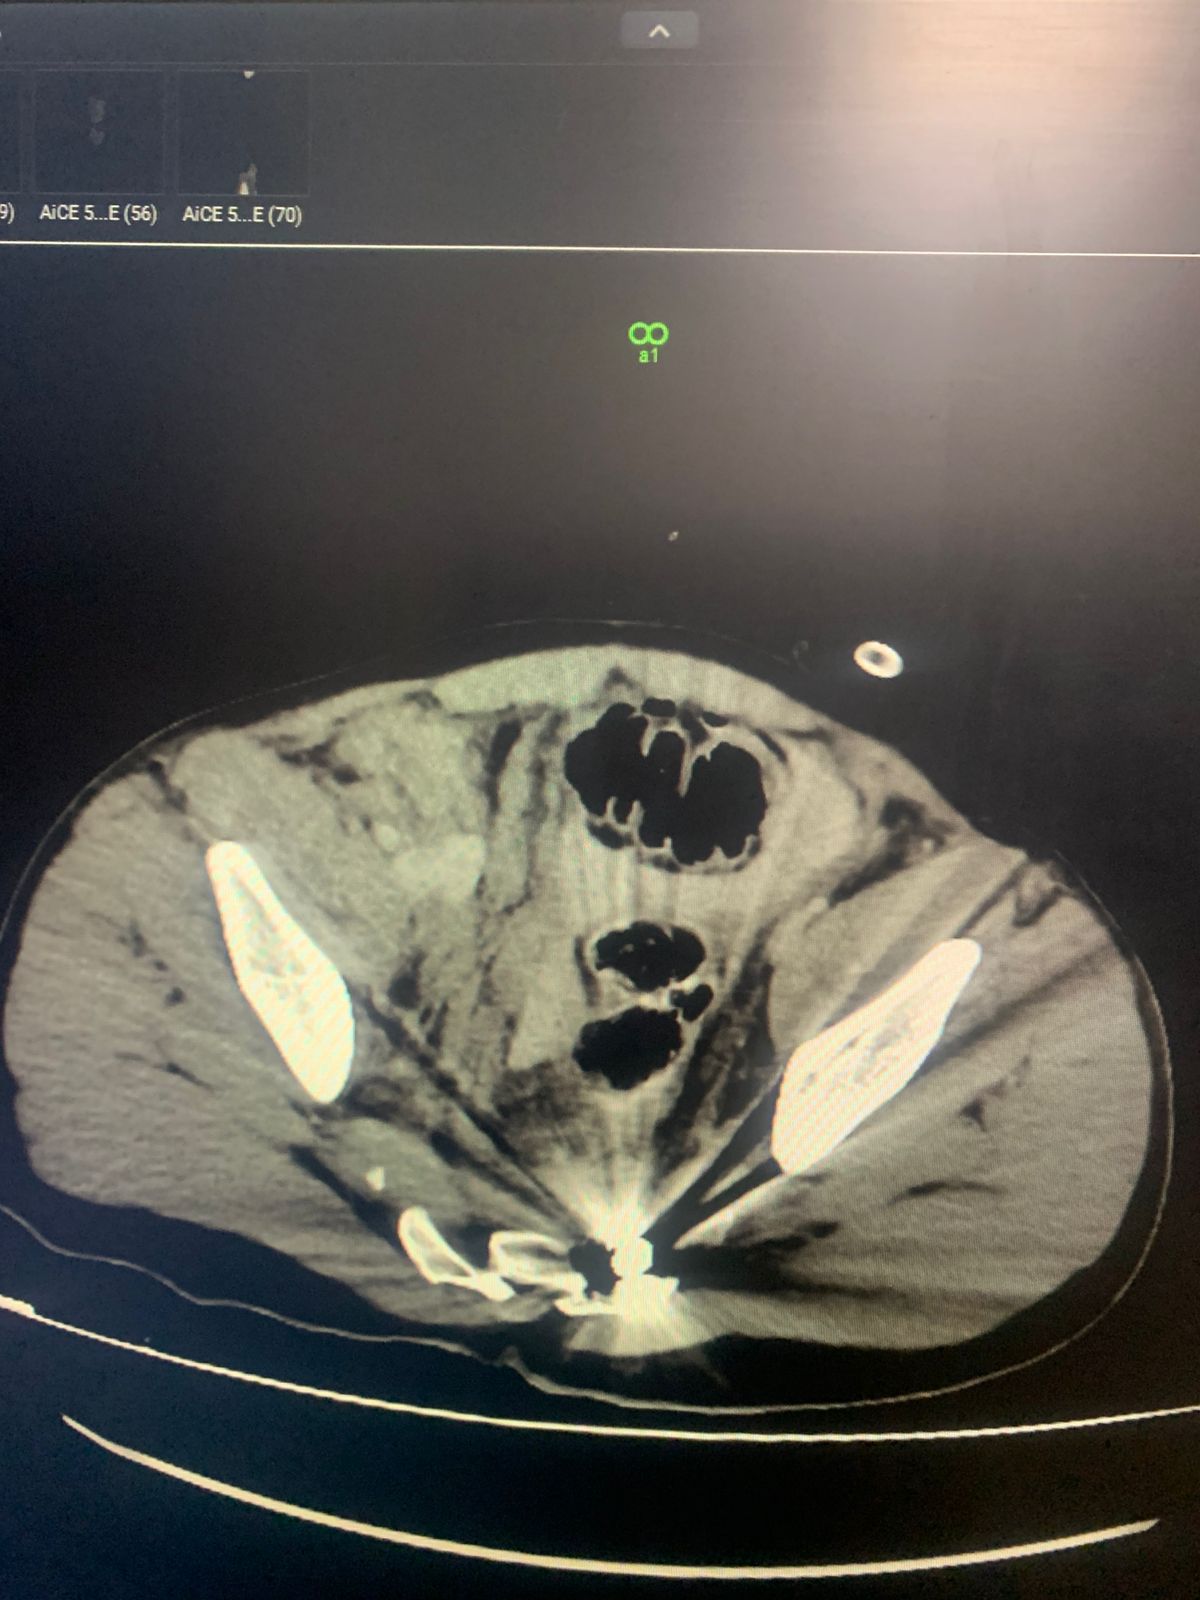

CT abdomen with IV and per rectal contrast

Findings :

. Bowel (sigmoid colon)perforation with leakage of contrast and Pneumoperitonium

. Moderate free fluid

. Portal venous gas

. Pseudoaneurysm of right external iliac artery

. Mild Bilateral pleural effusion